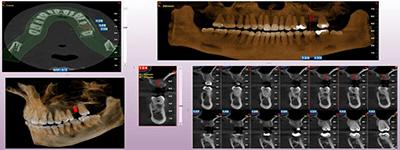

Proactive Dental Management thru our 3D Imaging Manipulation Software

With Oral Maxillofacial CT Scans, your dentist enhances his ability to proactively manage your health concern thru accurate diagnosis & better treatment planning. Moreover, the patient benefits from a painless,low radiation dose CT Scan procedure.